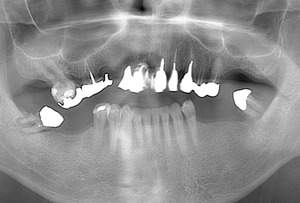

まずはオールオン4治療が可能か不可能か調べていきます。安全かつ確実に成功させるため、レントゲン撮影や歯周病の状態等のお口の基本的な検査を行います。

お口の状態の把握した後に、オールオン4治療をご希望の方は2回目の診察にて診査・診断を行います。こちらの診査ではCT撮影や噛み合わせの記録・顔貌評価・型取り等の細かい検査を行ってまいります。

インプラント周囲炎の予防は、レントゲンでの経過観察、正しいブラッシング、専門的に定期的なクリーニングやメンテナンスを受けることが必須となります。

インプラントを失ってしまうケースのほとんどがインプラント周囲炎によるものです。インプラント周囲炎とは、インプラントの周りに細菌等が溜まり炎症を起こし、噛み合わせや強い咬合力などでインプラントを支えている骨がなくなってしまう病気です。

歯周病と同じ様な症状があり、出血や歯肉の腫れを伴います。しかし痛みを伴わないことが多いため発見が遅れることが多いです。

したがってオールオン4然り、インプラントの長期的な寿命の安定を考えると患者様のセルフケアとプロによる専門的なメンテナンスを行うことがインプラント周囲炎予防となるのです。